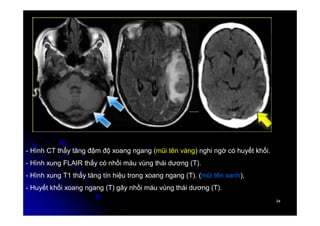

- Hình CT thấy tăng đậm độ xoang ngang (mũi tên vàng) nghi ngờ có huyết khối.

- Hình xung FLAIR thấy có nhồi máu vùng thái dương (T).

- Hình xung T1 thấy tăng tín hiệu trong xoang ngang (T). (mũi tên xanh),

- Huyết khối xoang ngang (T) gây nhồi máu vùng thái dương (T).